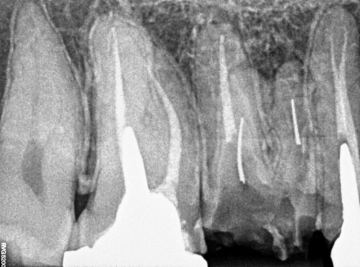

Dente 16 – Remoção de peça, pino metálico, limas fraturadas nos canais mv, mv2 e dv.

Neste caso específico há três partes de um pino metálico, que se partiu, aumentando ainda mais, a utilização das técnicas que foram implementadas. Vejam os passos nas fotos acima.